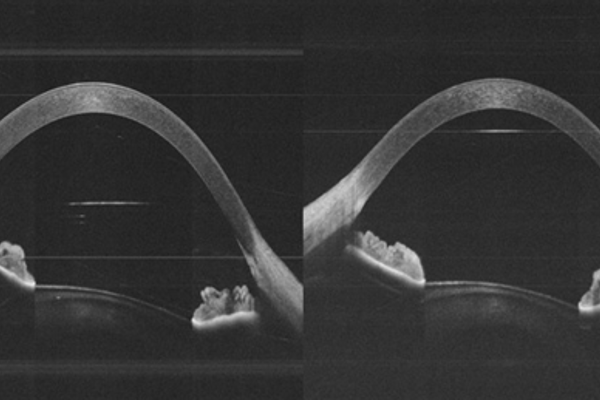

Optical coherence tomography – reinventing the eye examination